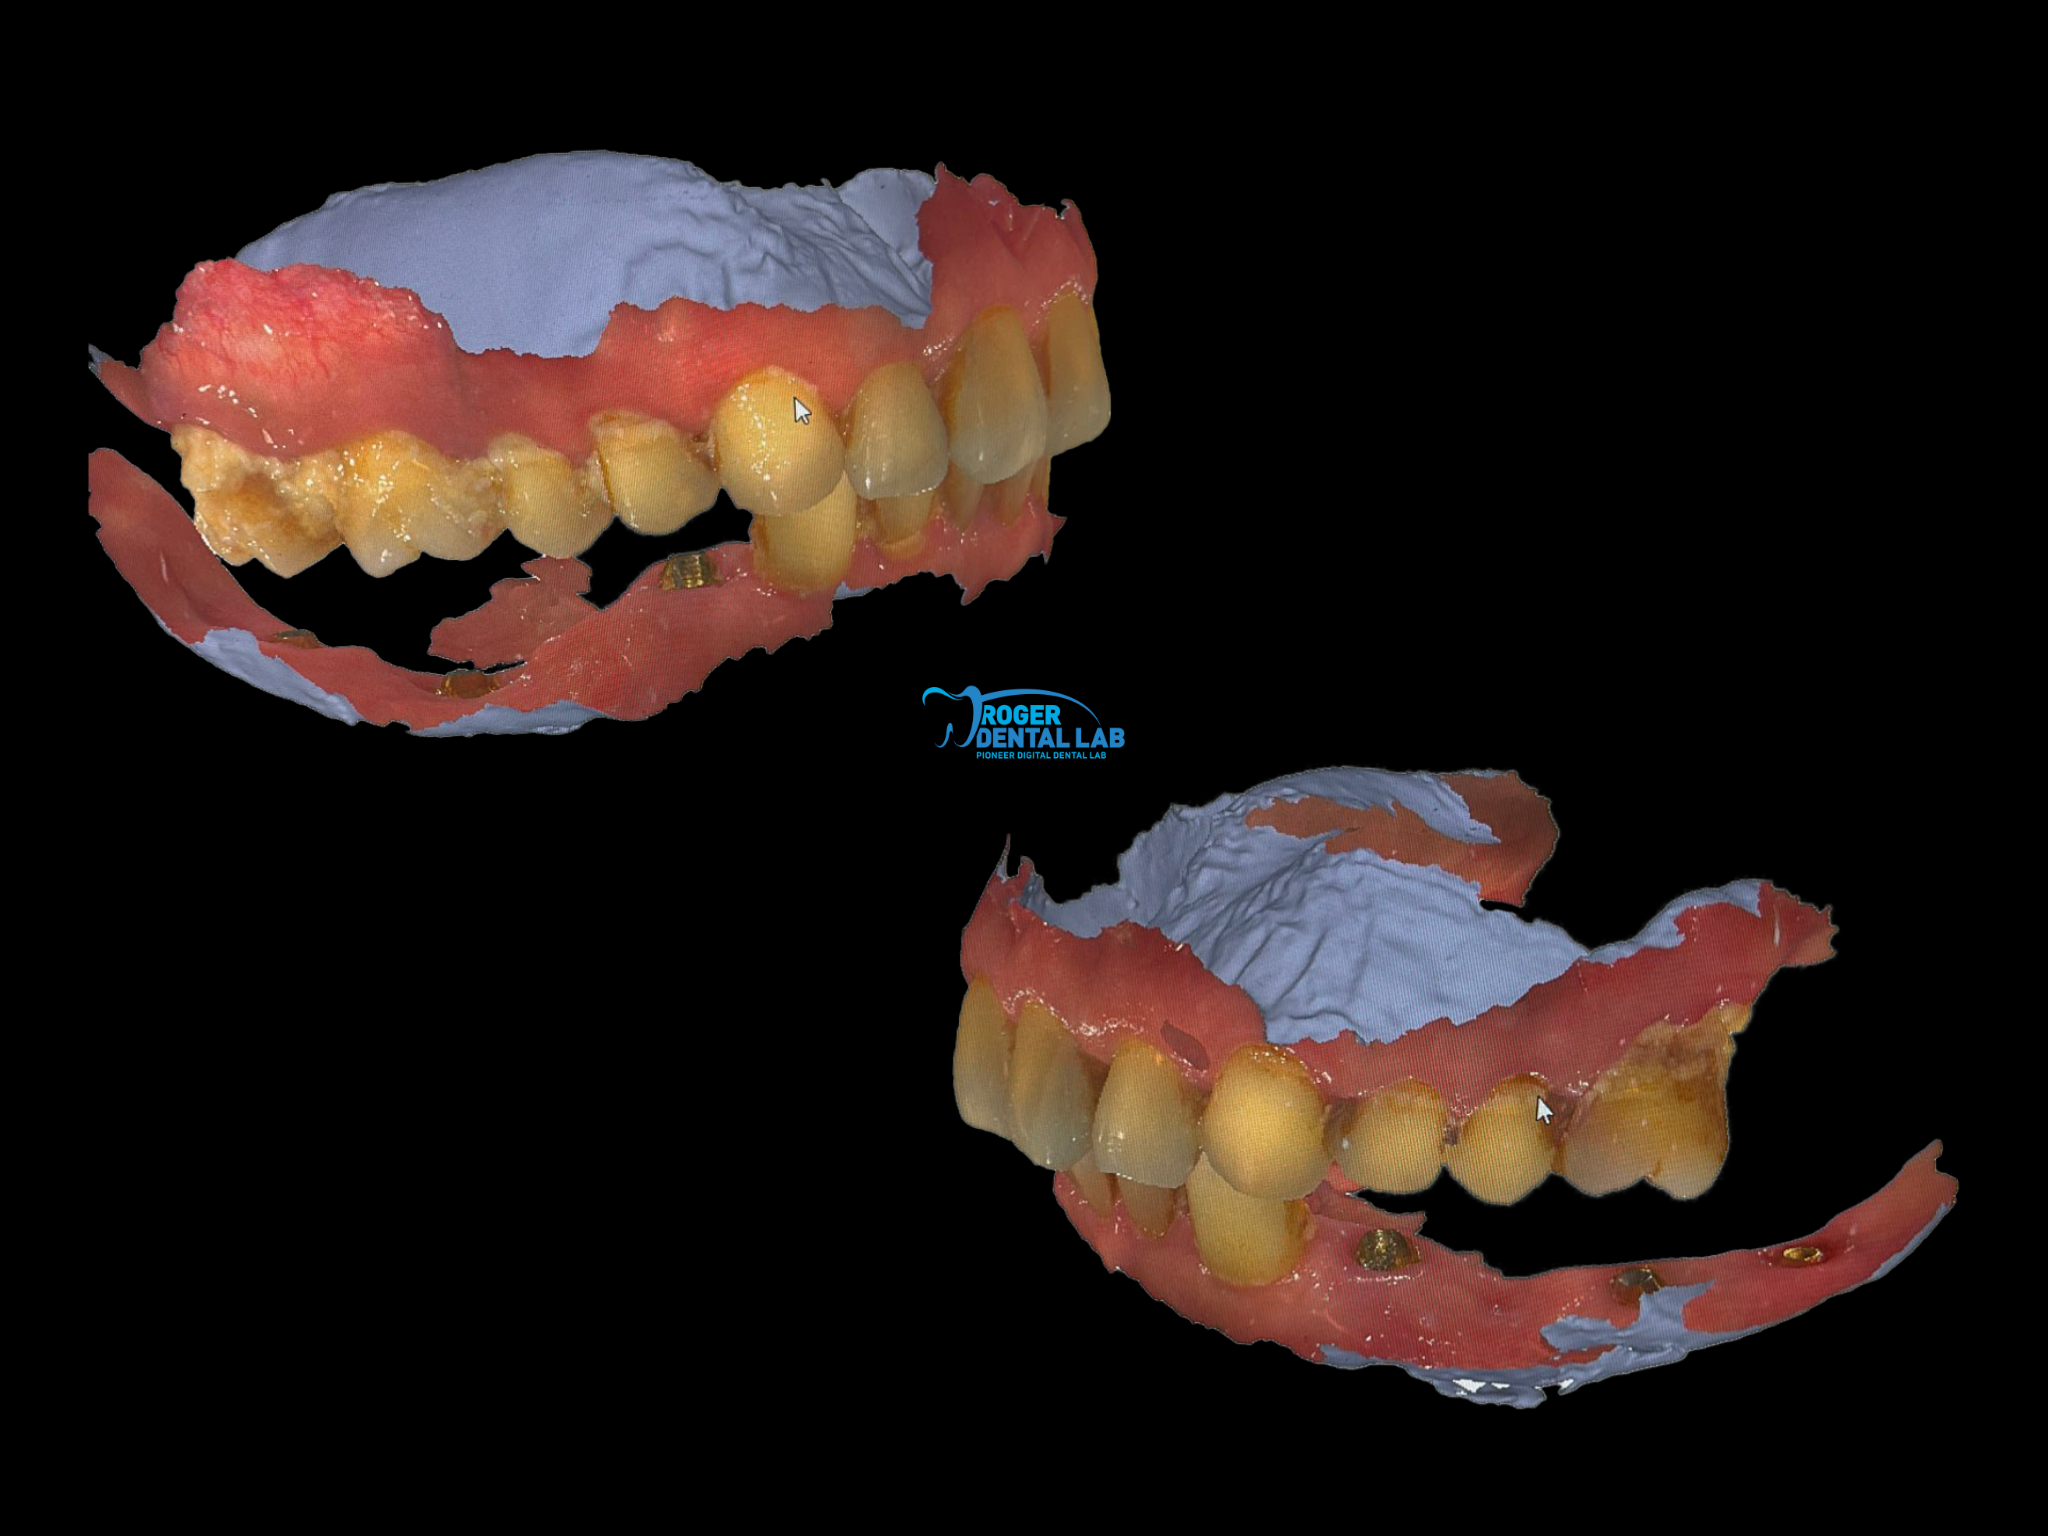

We support various types of Digital Intraoral Scanners – 3Shape TRIOS, Medit, SHINING 3D, iTero, etc.